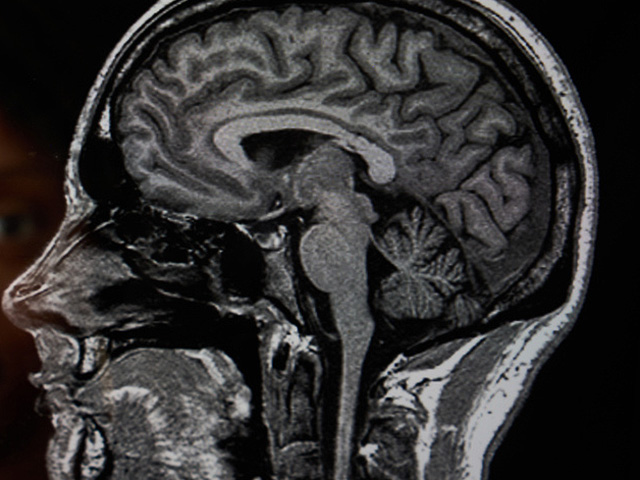

Скончался самый молодой человек с диагнозом деменция